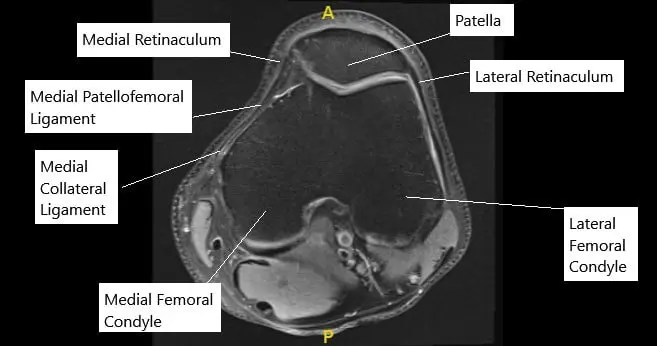

The kneecap sits in a small groove at the front of the thigh bone. As the knee bends, the kneecap moves up and down this groove. The medial patellofemoral ligament, located on the inner side of the knee, acts like a strap to prevent the kneecap from drifting outward. When this ligament is torn, the kneecap can shift out of place.

MRI of the knee in axial section showing normal MPFL.